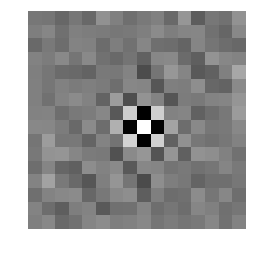

Medical image segmentation methods normally perform poorly when there is a domain shift between training and testing data. Unsupervised Domain Adaptation (UDA) addresses the domain shift problem by training the model using both labeled data from the source domain and unlabeled data from the target domain. Source-Free UDA (SFUDA) was recently proposed for UDA without requiring the source data during the adaptation, due to data privacy or data transmission issues, which normally adapts the pre-trained deep model in the testing stage. However, in real clinical scenarios of medical image segmentation, the trained model is normally frozen in the testing stage. In this paper, we propose Fourier Visual Prompting (FVP) for SFUDA of medical image segmentation. Inspired by prompting learning in natural language processing, FVP steers the frozen pre-trained model to perform well in the target domain by adding a visual prompt to the input target data. In FVP, the visual prompt is parameterized using only a small amount of low-frequency learnable parameters in the input frequency space, and is learned by minimizing the segmentation loss between the predicted segmentation of the prompted target image and reliable pseudo segmentation label of the target image under the frozen model. To our knowledge, FVP is the first work to apply visual prompts to SFUDA for medical image segmentation. The proposed FVP is validated using three public datasets, and experiments demonstrate that FVP yields better segmentation results, compared with various existing methods.